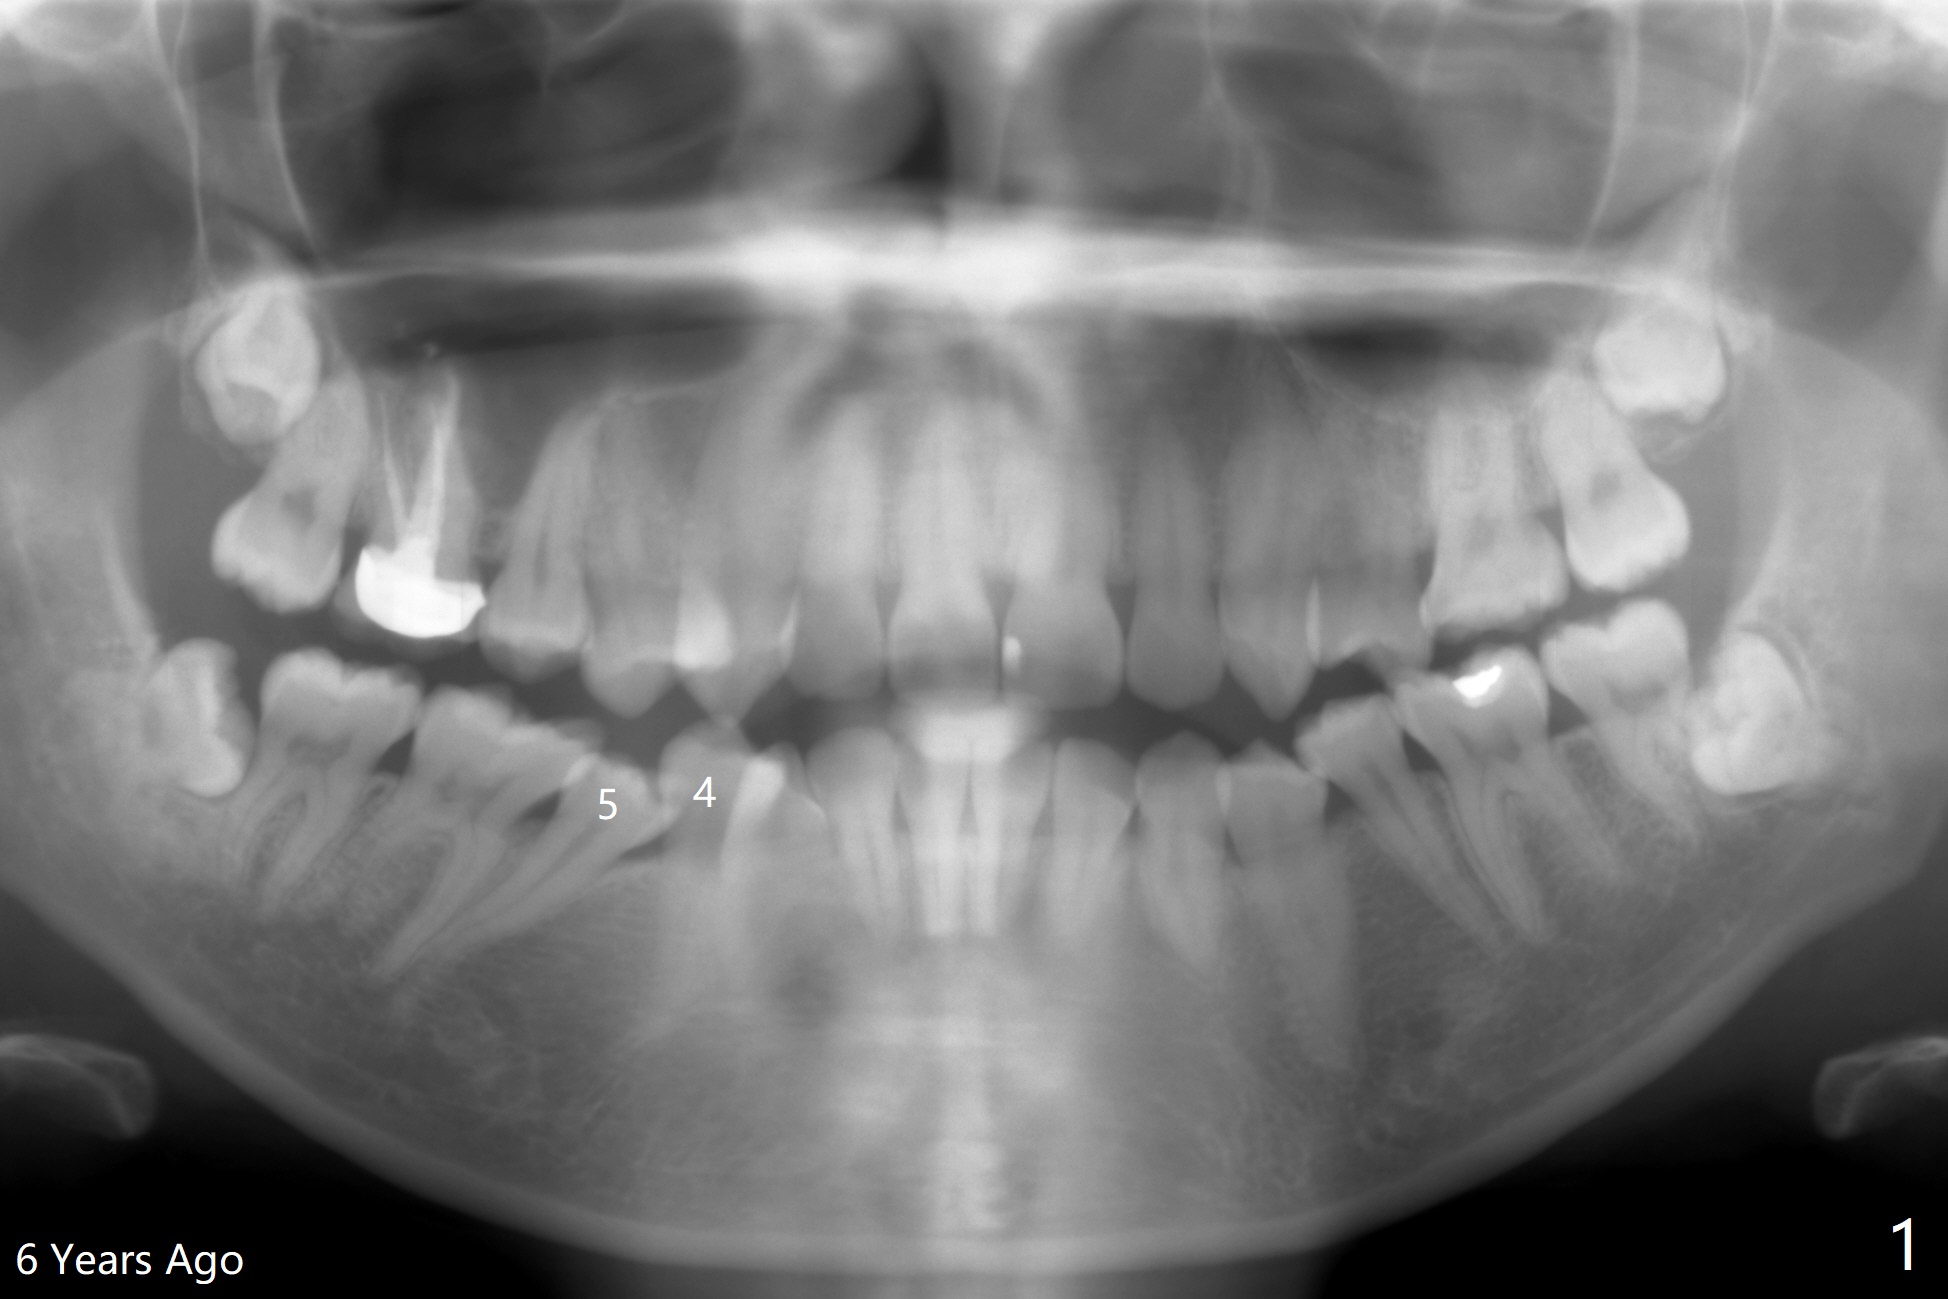

A 34-year-old woman with crowding particularly at LR 4/5 (Fig.1) and suspected DO caries of LR4 (Fig.2) returns with symptom of pulpitis and "cavity" at LR5 (MO). New Bitewing confirms LR4 DO caries (Fig.3). Treatment plan is to extract LR4 and place composite at LR5 if present. Extraction turns out to be difficult because of nervousness and TMD of the patient and crowding. The proximal areas of LR4 requires removal before luxation without traumatizing the neighboring teeth (Fig.4 insert black areas). In fact there is no caries at LR5. When the patient returns for orthodontic treatment, bracketing at LR5 should consider overcorrection (Fig.5 (black rectangle vs. red line: height of contour)) due to the tilted long axis (Fig.1).